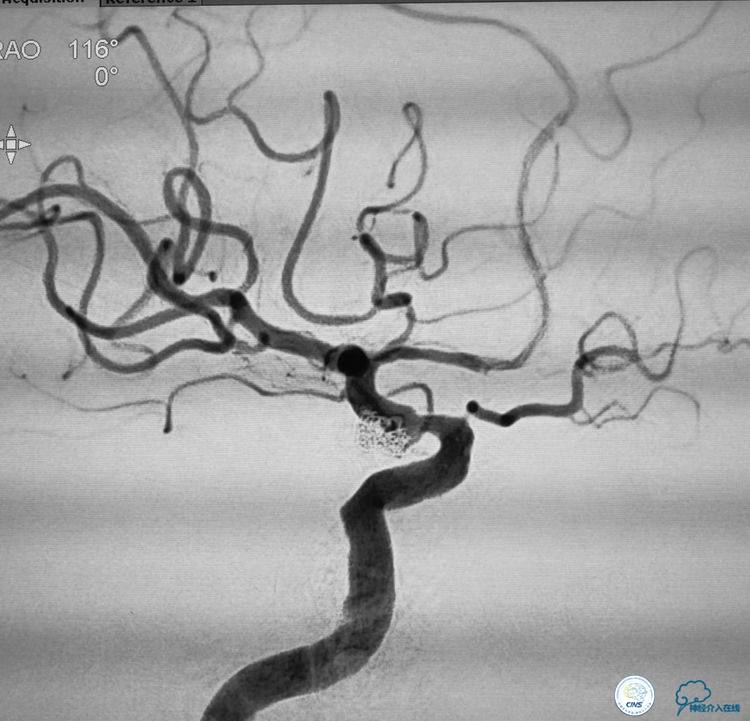

▼动脉瘤致密栓塞,血管狭窄改善,载瘤动脉通畅。

治疗策略:采取支架辅助弹簧圈栓塞治疗动脉瘤。但由于动脉瘤近端的血管狭窄,如果不实施对狭窄血管的干预,支架释放后,很可能会导致支架打不开或者导致血管闭塞。因此首先对动脉瘤近端的狭窄血管进行球囊扩张,扩张的危险性就是有可能会导致动脉瘤的破裂。因此我们选用了超柔顺性的球囊。球囊扩张之后置入支架,由于动脉瘤呈分叶状,所以我们选择了双微导管支架辅助弹簧圈栓塞治疗这例动脉瘤,取得了良好效果。